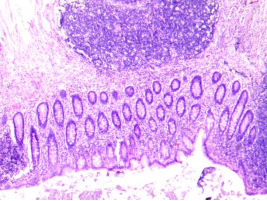

单纯性阑尾炎

阑尾表面充血,腔中有中性粒细胞渗出,肠壁各层有少量中性粒细胞浸润,血管充血。

阑尾固有层淋巴组织结构保存完整,

正常黏膜区域之间有轻微的

局灶性炎症和溃疡